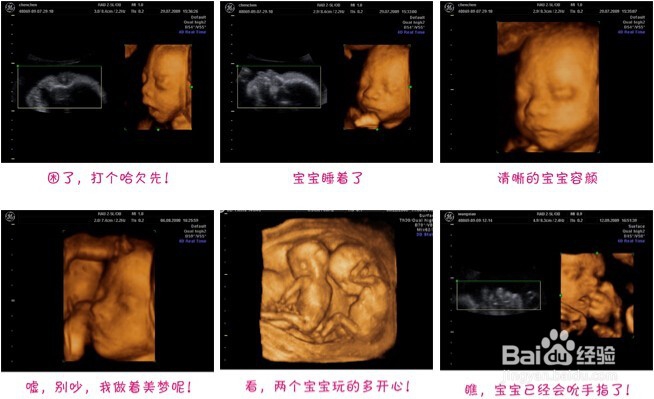

2、其实做B超,也没有必要每个月都做。怀孕后第一次检查了,也会照B超,之后没有什么不舒服的话,就可以等16-20周的时候做个四维彩超。